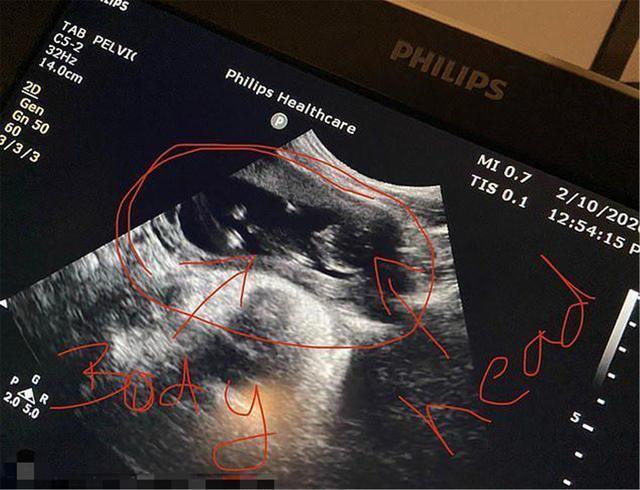

然而,2014年他生下了大女儿阿扎莉娅,如今又怀上了二胎,已经7周了。

凯登有个29岁男友,他们都表示对第二个孩子极为期待。